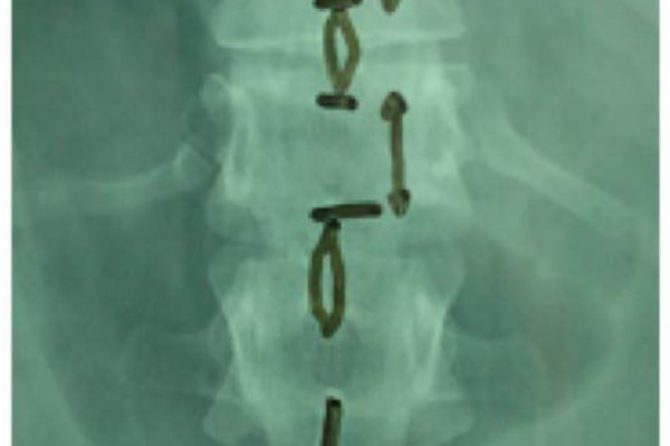

Upon admission, palpation revealed tenderness at the thoracolumbar region. His neurologic examination was normal with no motor or sensory deficit of the lower and upper limbs. Ultrasonography was performed to exclude blunt abdominal concomitant injuries. Simple radiographic evaluation of the cervical spine, thorax and pelvis did not demonstrate associated injuries. Radiographs (Figs. 1, 2) and CT scans (Fig. 3) of the thoracolumbar spine revealed a transverse fracture at the level of T12. The CT scan further demonstrated a split of the posterior elements, progressing anteriorly into the vertebral body. Conservative treatment was decided and the patient, following an initial period of bed rest, was mobilized wearing a thoracolumbar orthosis. Appropriate antithrombotic prophylaxis with low molecular weight heparin was administered, until full ambulation was achieved. The patient was followed up with serial thoracolumbar radiographs for the first 6 weeks of ambulation and later on, in one month intervals. The thoracolumbar orthosis was applied for three months. At the 5th month follow-up, he was pain free with radiographic signs of mild vertebral kyphosis. Upon completion of treatment, he returned successfully to pre-injury levels of daily activity, without any impairment.

Fig. (2). Anteroposterior (AP) radiograph demonstrating increased interspinous distance at the level of injury.